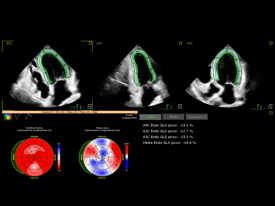

Dr. Arcangelo Giampa’ specialista cardiologo presso UMIMED Centro Medico Castagna di Darfo Boario Terme, ASST Valcamonica e ASST Spedali Civili di Brescia. Ho al mio attivo una vasta esperienza nel settore cardiologico in ambito clinico e nella diagnostica strumentale non invasiva ed ho partecipato a numerosi eventi in ambito nazionale ed internazionale.

con i nuovi software di intelligenza artificiale e imaging vascolare tridimensionale